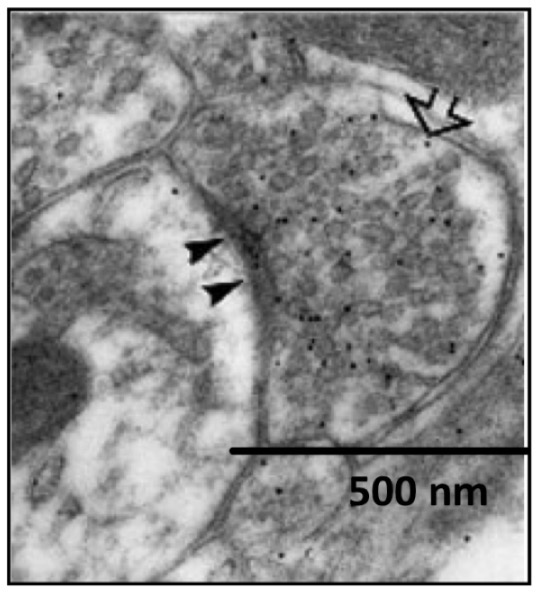

In this electron micrograph, what do the black dots represent?

Specific antibodies labelled with gold particles used to detect the presence of GABA

Where are GABAergic synapses found?

Dendrites

Soma

Axonal Initial Segment (AIS)

Why so inhibition at the Axon Initial Segment (AIS) especially powerful?

Can strongly inhibit the initiation of action potentials